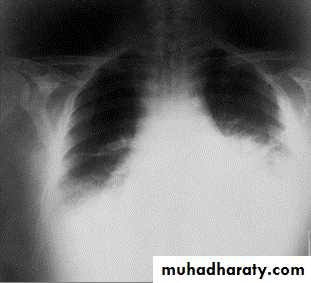

Mediastinal widening and pleural effusion on Chest X-Ray in inhalational anthrax

Hemorrhagic meningitis due to inhalation anthrax